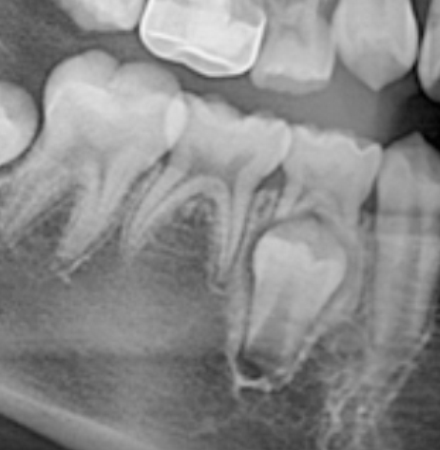

2차 스크러닝

x-ray를 통해 육안으로 관찰되지 않는 부분을 파악